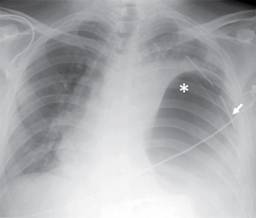

Figura 1: Radiografía PA de tórax que muestra radioopacidad en hemitórax izquierdo, inseparable de estructuras mediastinales asociada a imagen radiolúcida de aspecto redondeado, la cual condiciona desplazamiento de tráquea hacia la derecha (punta de flecha). Nótese la ausencia de burbuja gástrica en topografía habitual, se aprecia imagen sugestiva de fondo gástrico en hemitórax izquierdo (1), presencia de sonda pleural que penetra por sexto espacio intercostal izquierdo con dirección apical (flecha).